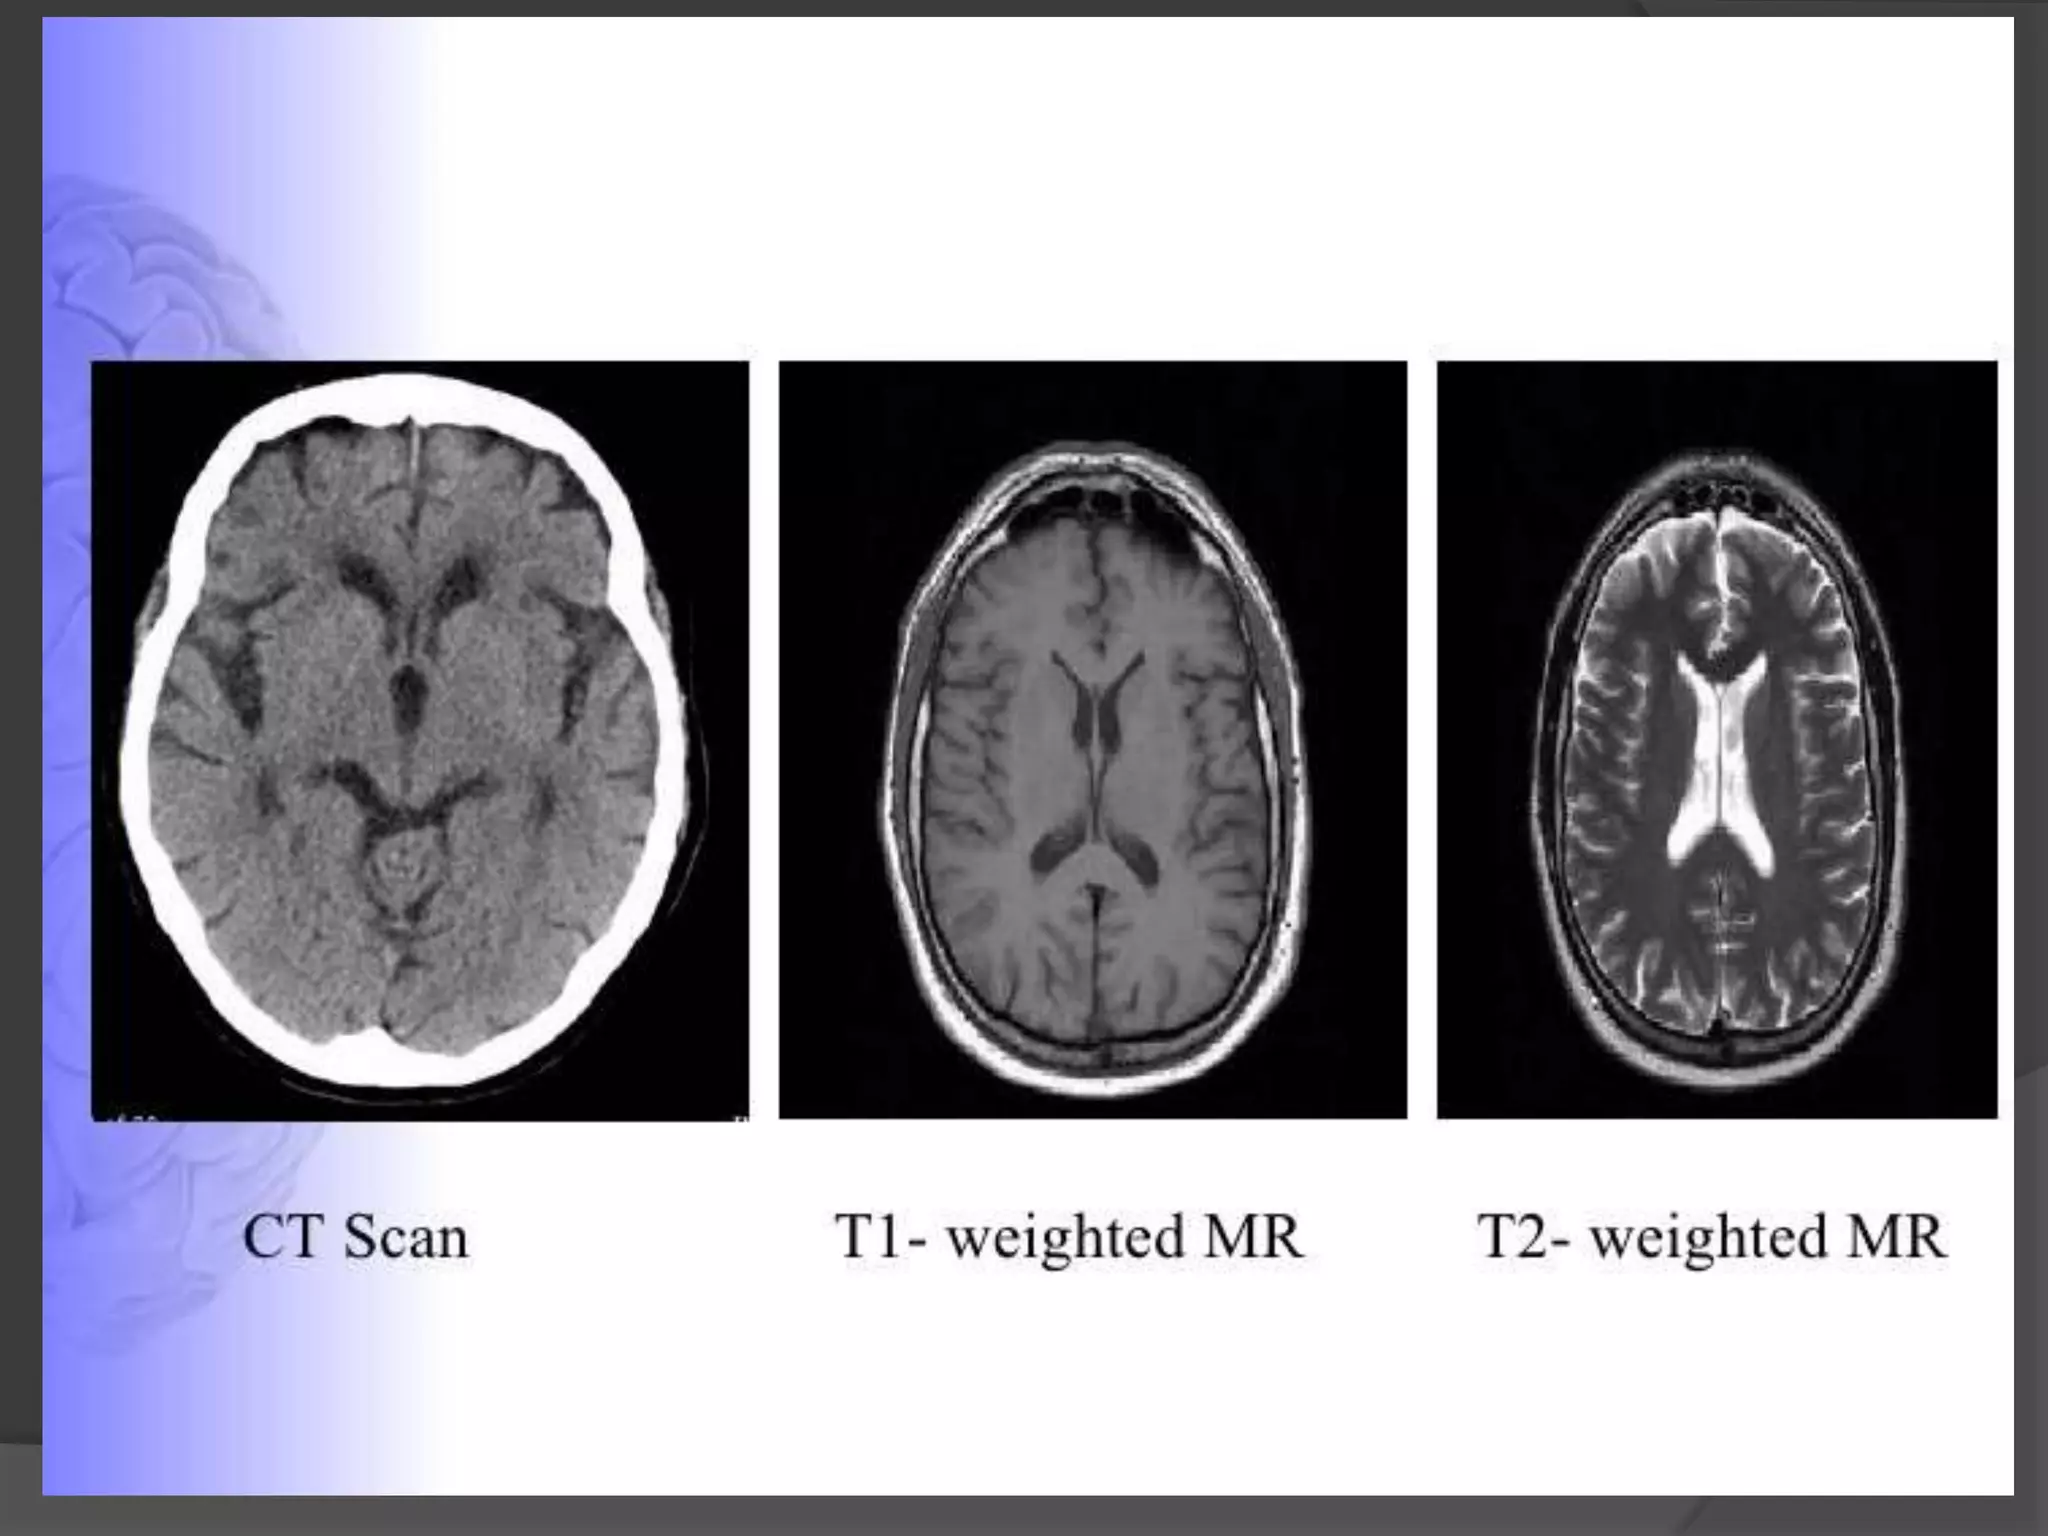

COMPUTED TOMOGRAPHY (CT)

…Contd

CT Scanners take a

series of head X-ray

pictures from all

vantage points

The amount of radiation

that passes through, or is

not absorbed from, each

angle is digitized &

entered into a computer

When viewed in

sequence, the images

allow mental

reconstruction of the

structure of the brain

BASICS

360º around a

patient's head

The computer uses matrix algebra

calculations to assign a specific

density to each point within the head

& displays these data as a set of 2-D

images

Grey-scale Appearance on CT

Tissue

Appearance

Bone

White

Calcified Tissue

Clotted Blood

Grey Matter

Light Gray

White Matter

Medium Grey

CSF

Near Black

Water

Air

Black

Points to remember



CT image is determined only by degree to which tissues absorb X-ray

Bony str. Absorb large amount of x-rays and tend to obscure the details

of neighboring structures poor visibility in brainstem.

Poor differentiation of grey-white pattern than compared to MRI.

T1 Weighted MRI

Best for visualizing normal

neuroanatomy

Sharp boundaries between

grey matter, white matter, and

Useful in evaluation of

cerebro-pontine angle cistern

& pituitary fossa

Bone white

white matter light grey

grey matter medium grey

water/CSF/air- Black

T2 Weighted MRI

Less distinct boundaries

between white and grey matter

Best for displaying pathology

Useful in demyelination, edema

& tumour infiltration

Gray matter medium gray

white matter dark grey

CSF and water White